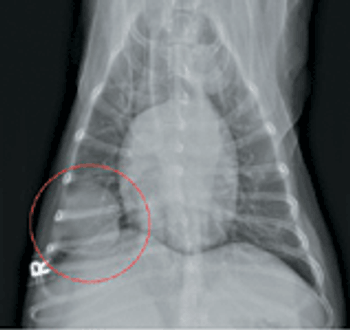

Correct answer Image Quiz: A skinny Lab with a swollen face